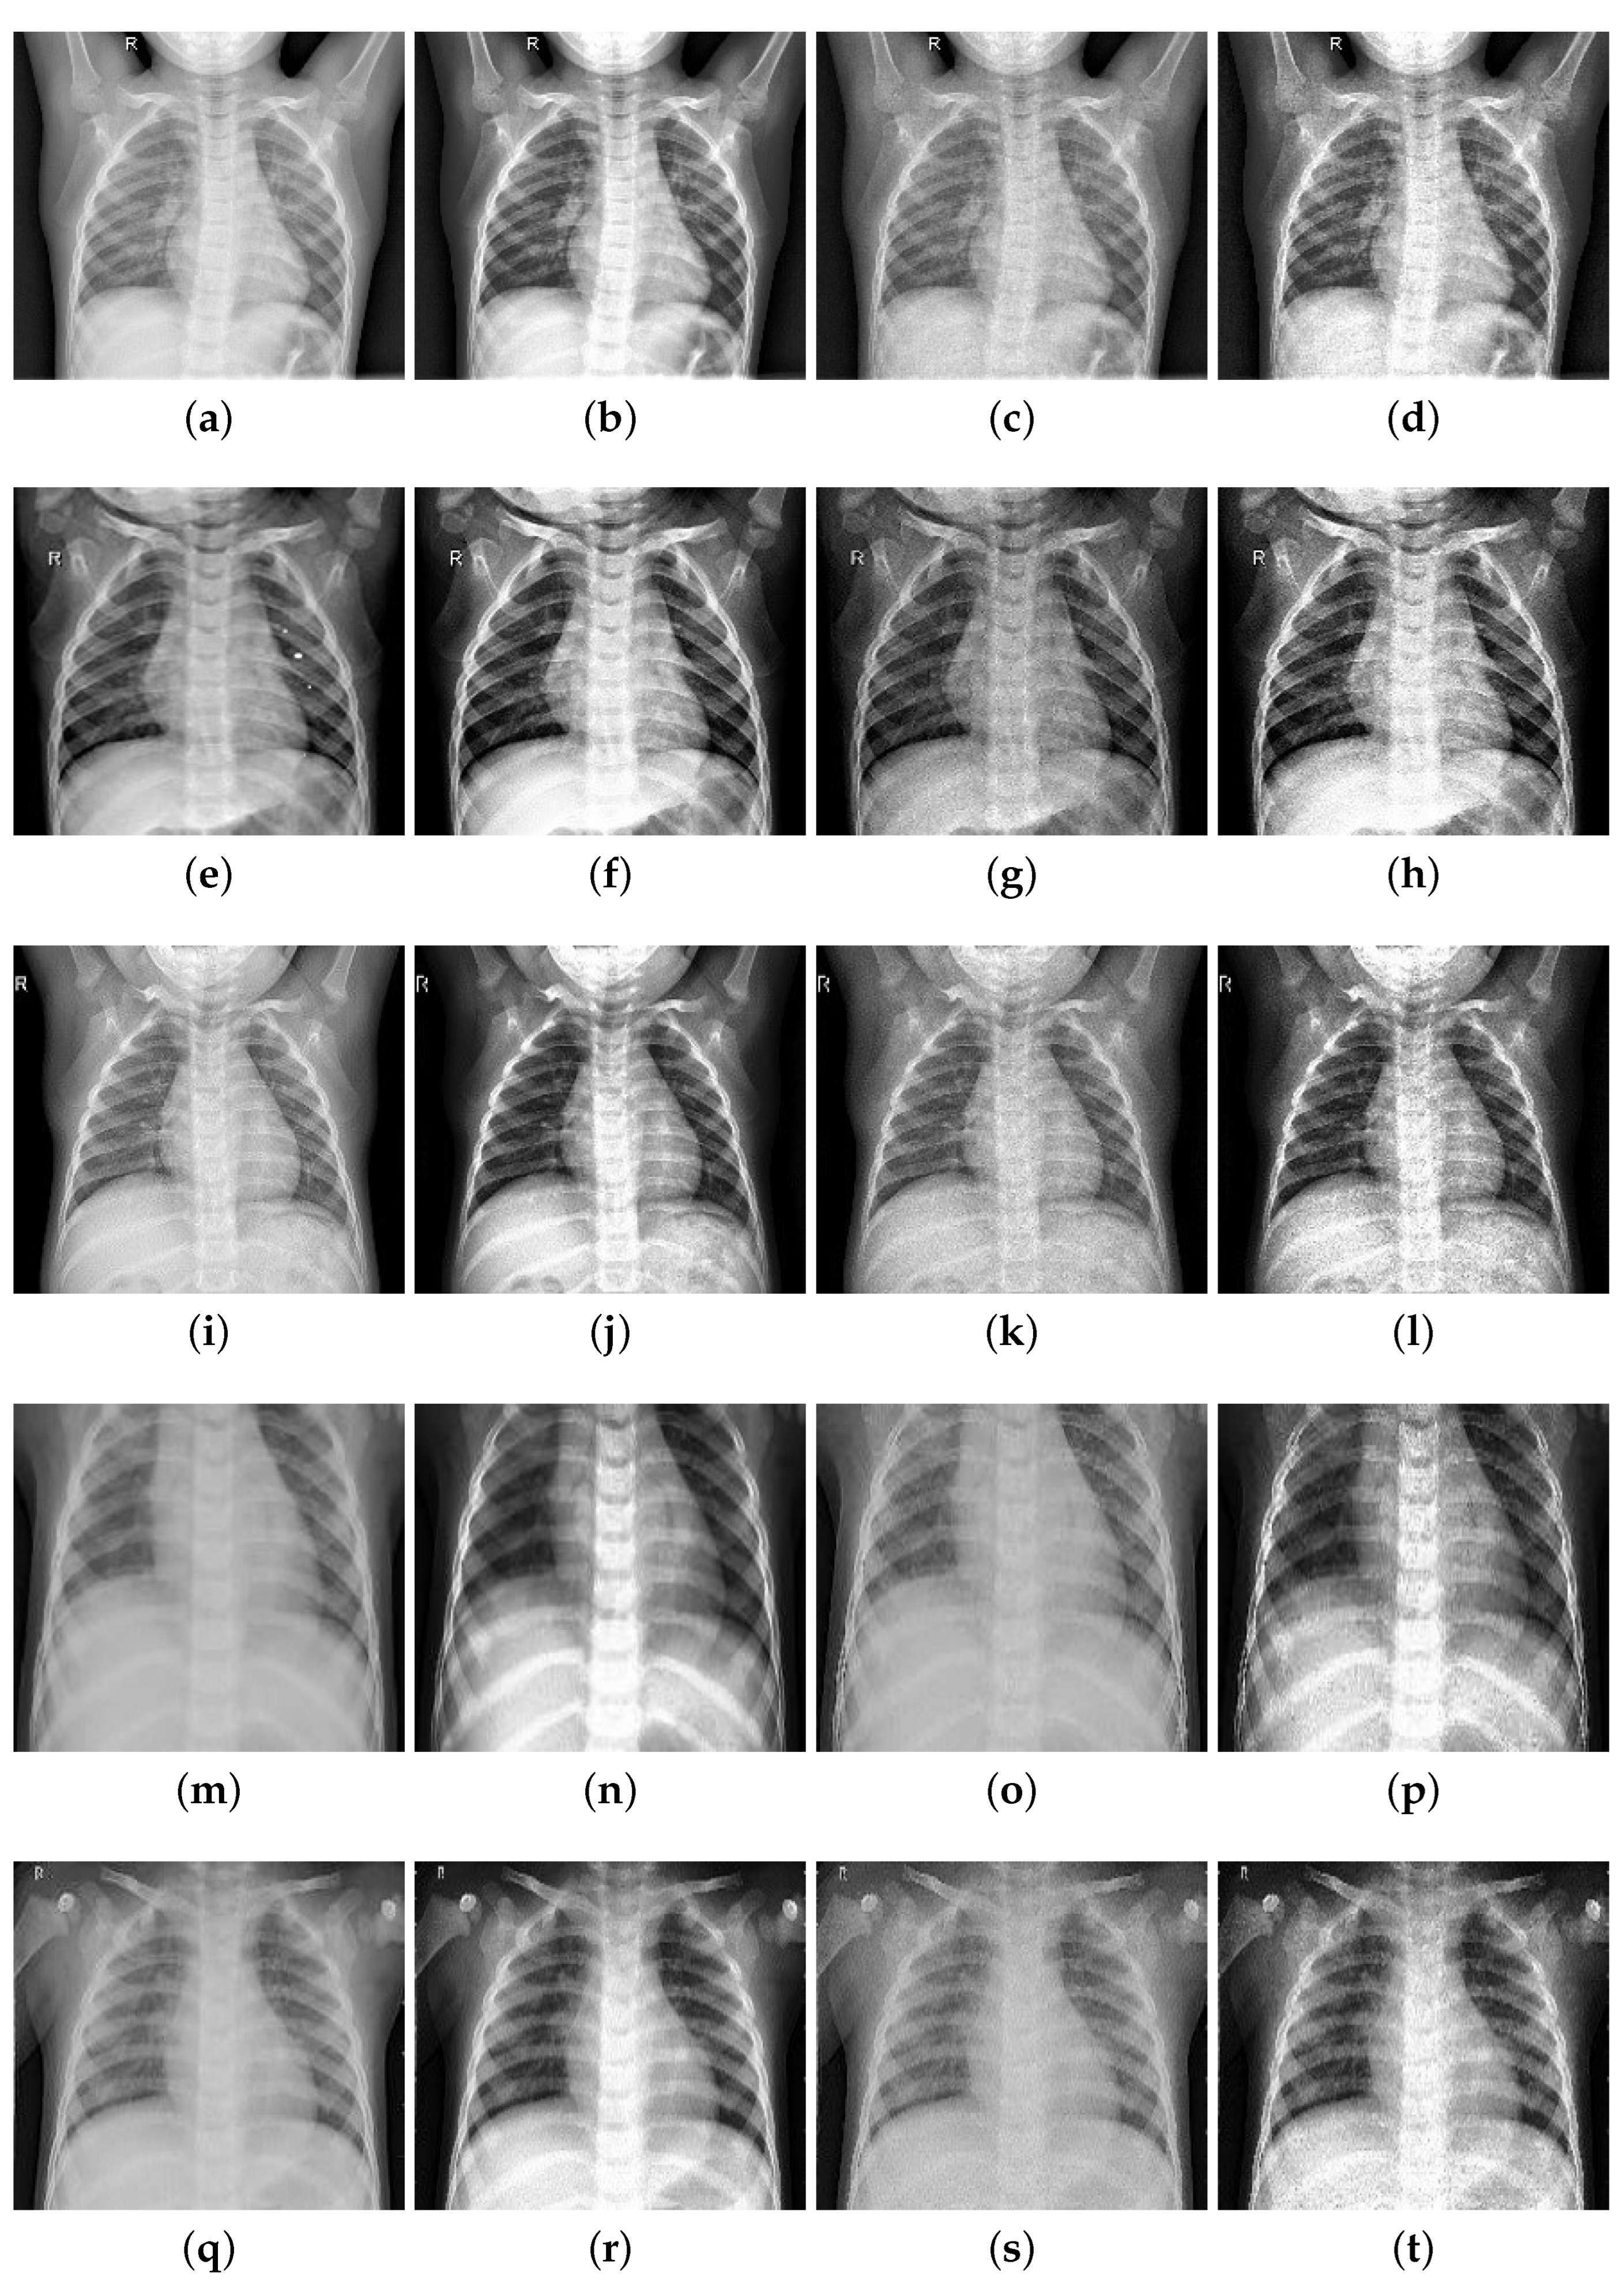

To improve the authenticity of the research, this paper selected a large number of athletes from professional sports colleges. X-ray images of the above athletes’ lungs were collected. There were 2806 men and 2806 women, totaling 5612, accounting for 30% of the unit athletes in 2020. The ages were between 18 and 25 years old. The shortest training period was only 1 year and the longest training period was 5 years. Figure 6 and Figure 7 are the medical images of the part collected.

A total of 5612 original grayscale images were collected and randomly clipped to 224 × 224 grayscale images, with the pixel value divided by 255 to normalize the data, thereby accelerating the training process. Finally, the data were divided into a training set, a validation set and a test set at a 8:1:1 ratio, which is convenient for the training and evaluation of subsequent models.

In order to test the effectiveness of image enhancement methods, this paper uses the methods of contrast enhancement and edge coefficient enhancement to enhance the athlete lung medical images. Five medical images were taken as examples (1, 2, 3 without pneumonia; 4, 5 with pneumonia) and image enhancement was performed on these five images. The original images, the images with enhanced contrast, the images with enhanced edge information, and the images with integrated enhancement are shown in Figure 8.

Figure 6. Lung image without pneumonia.

Figure 8. Image enhancement effect comparison image: (a) original-1; (b) contrast boost-1; (c) enhanced edge-1; (d) integrated-1; (e) original-2; (f) contrast boost-2; (g) enhanced edge-2; (h) integrated-2; (i) original-3; (j) contrast boost-3; (k) enhanced edge-3; (l) integrated-3; (m) original-4; (n) contrast boost-4; (o) enhanced edge-4; (p) integrated-4; (q) original-5; (r) contrast boost-5; (s) enhanced edge-5; (t) integrated-5.